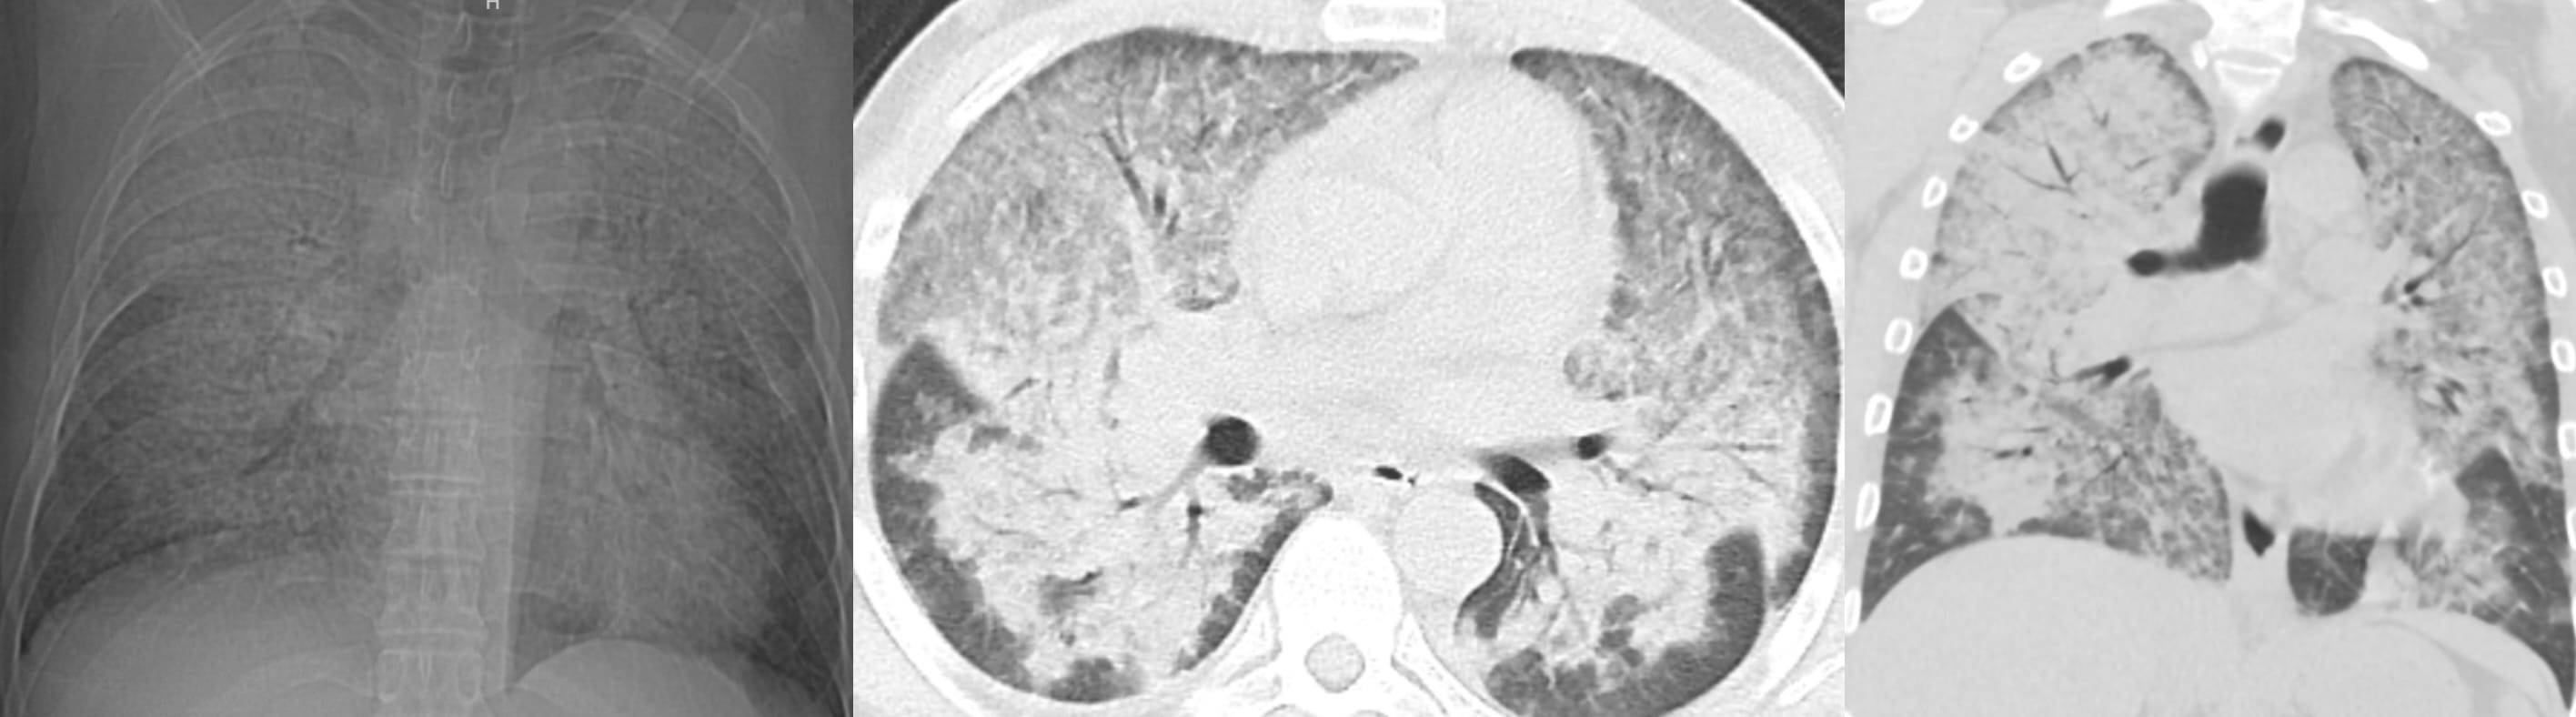

CT of Acute Lung Injury Edema

Don’t confuse the posterior lung opacities with anything else other than consolidated and —particularly—atelectatic lung. This is potentially so-called recruitable (by different ventilatory strategies) lung.

The concepts of (dorsal) “sponge” and (ventral) “baby” lungs are evocative. The size of the ventral aerated lung in ARDS (with the patient supine) suggests a “baby” lung— as conceptualized by Gattinoni et. al.

There is relatively more lung volume in the dorsal lungs.